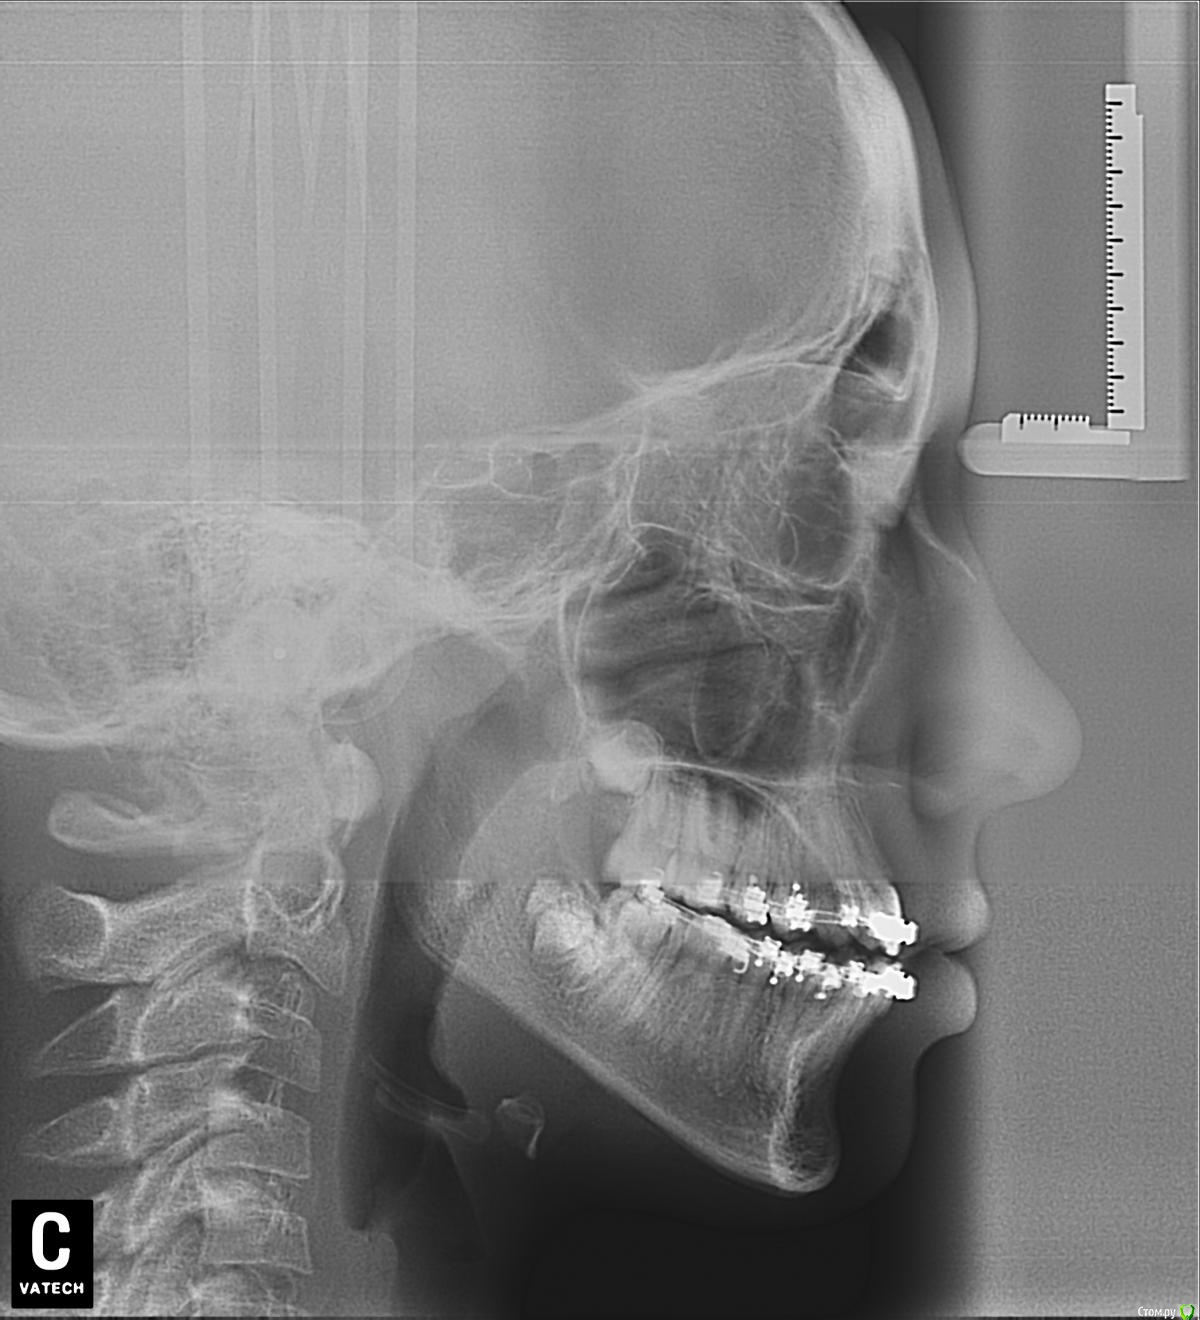

Мама пациента Опубликовано 20 мая, 2016 Поделиться Опубликовано 20 мая, 2016 Письмо на форум стоматологов. Здравствуйте, уважаемые доктора. Извините за много букв, но короче не расскажешь. Дочери 12 лет. Никогда не замечала перекрёстного прикуса, вдруг в июне 2015 г. на регулярном осмотре терапевт сказала, что прикус перекрестный, нужно срочно бежать к ортодонту, а то ребенок «съест» зубы, хотя раньше не говорили об этом. Видимо поспешили с выбором врача. Доктор хорошая, старательная, молодая, но видимо у нас не совсем линейная ситуация, с которой раньше она не сталкивалась. Здоровье, к сожалению, у ребенка не богатырское, парез лицевого нерва был с рождения, дисплазия соединительной ткани – исследованиями не подтвержденная (много гибкости, мало силы и упругости мышц). Поставили брекеты на верхние зубы в июле 2015- 11 лет. Нижнюю челюсть наклеили в ноябре. ОПГ снимок до того прилагается. Кроме него исследований не делали, теперь поняла, что надо было. Все поездки к врачу заканчиваются 3-х-5-ти дневными страданиями. В марте после поездки (наклеили клыки, прорезающиеся нижние 7-ки и поменяли дуги), на следующий день поднялась тем-ра 37,7 и потом 3 недели!!! она была субфебрильная. Анализы крови и м. были нормальные (немного снижены сегментоядерные и повышены лимфоциты). Это сопровождалось головокружением. Лечили синусит. По ВСД по назначению невропатолога сделали исследования (ЭЭГ, УЗДГ- ТГ)- повышено внутричерепное давление (результаты есть). Сделали 4 сеанса у мануального тер., который по его словам «снял блок с шеи…и сделал спину (убрал начинающийся сколиоз)». Головокружения прекратились. Сходили на консультации к хорошим ортодонтам в Москве, к сожалению, никто пока помочь не берется. После одной из консультаций (врач достаточно активно двигала челюсть) опять кружилась голова в течении пары часов. На консультации к челюсно-лицевым хирургам пока не попали, т.к. в Москве к гуру целая история попасть, а конец учебного года и два пропущеннных месяца в школе. Но операцию делать я ей не буду, т.к. риски для здоровья от операции гораздо выше. Будет взрослая сама решит. Случай не простой, время упущено, челюсть выросла криво, но рост еще идет (доктор сказал по ренгену ладони). Неужели в стране нет специалиста, который в комплексе занимается ортодонтией с содружестве в неврологами и мануальными (краниальными) терапевтами. Может кто-то занимается миотерапией (лечебная физкультура для челюстей). Сейчас просто боимся идти к ортодонту менять дуги и доклеивать отвалившиеся брекеты и я, и ребенок. Потому, что 4 недели мучений и по учебе уже пропустили пол-четверти. Ей хочется все бросить, оторвать все брекеты и забыть, как страшный сон. Хотя я прекрасно понимаю, что таким прикус оставлять нельзя, надо попытаться что-то сделать. Что бы вы делали для своего ребенка в этой ситуации? Ссылка на комментарий

Мама пациента Опубликовано 20 мая, 2016 Автор Поделиться Опубликовано 20 мая, 2016 Лицо Ссылка на комментарий

Yana guapa Опубликовано 20 мая, 2016 Поделиться Опубликовано 20 мая, 2016 при перекрестном прикусе я бы не ставила брекеты на нижнюю челюсть. Потому что дуга дает расширение (а у вас итак нижняя челюсть больше верхней) если и ставлю брекеты на нижнюю челюсть, то на верхнюю челюсть изнутри (с небной стороны) ставятся кнопки, и пациент носит косые эластики (плюс все зубы должны быть разобщены на накусочных площадках, иначе они никогда не смогут "перепрыгнуть" через бугорки нижних) у вас такого разобщения не вижу, верхние зубы упираются в нижние. здесь хоть кучу дуг поменяй, но все будет стоять на месте. ортодонты, занимающиеся в содружестве с мануальными терапевтами, неврологами И так далее - на каждом углу. только вот результаты..... причина ваших головокружений так и не выяснена? когда нибудь были такие головокружения до постановки брекетов? Ссылка на комментарий

Мама пациента Опубликовано 20 мая, 2016 Автор Поделиться Опубликовано 20 мая, 2016 (изменено) У нее и сильно стало лицо перекошено осенью, когда нижние наклеили. Люди стали видеть, что она кривит лицо, хотя до этого никому в глаза не бросалось сильно. Изменено 20 мая, 2016 пользователем Мама пациента Ссылка на комментарий